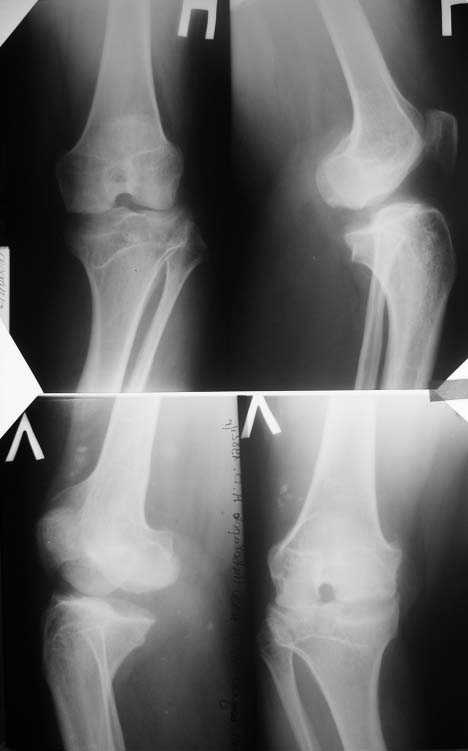

Прямая и боковая обоих коленных суставов